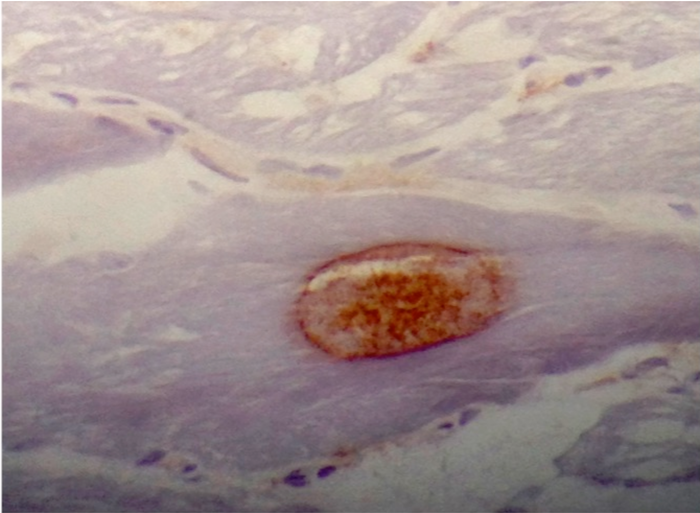

Positive stains

- Gomori trichrome shows rimmed vacuoles and can show ragged red fibers in areas

- Congo Red (amyloid) positive "apple-green" birefringence positive inclusions (Arch Neurol 1991;48:1229)

- Ubiquitin and LC3B highlight the inclusions

- Ubiquitin, B-amyloid, B-amyloid precursor protein (APP), α-synuclein, tau, TDP43, and LC3B can be seen in the inclusion bodies

- CD8+ T lymphocytes highlight the inflammatory response and infiltrate non-necrotic myofibers